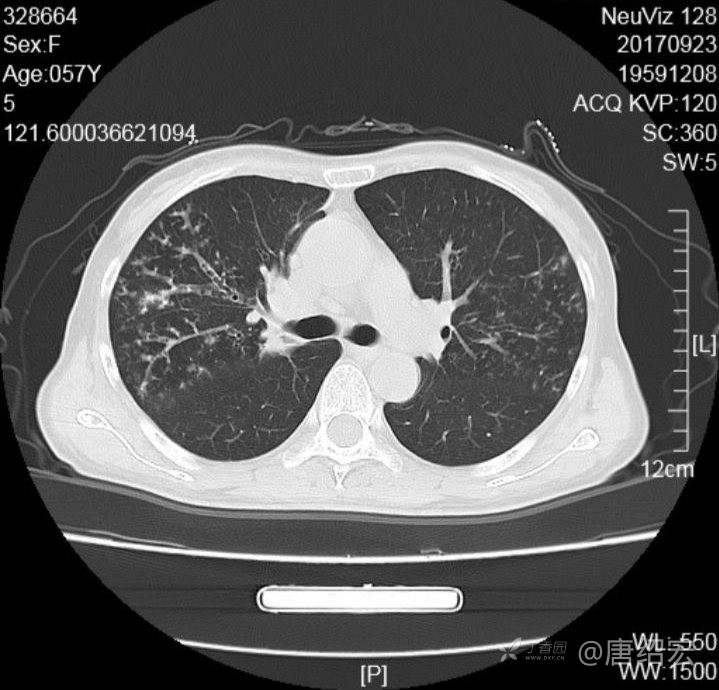

中年女性满肺树芽征还有支气管扩张,考虑什么疾病?

女,57岁,

主诉:发热、咳嗽、咯黄痰,胸闷3天入院。